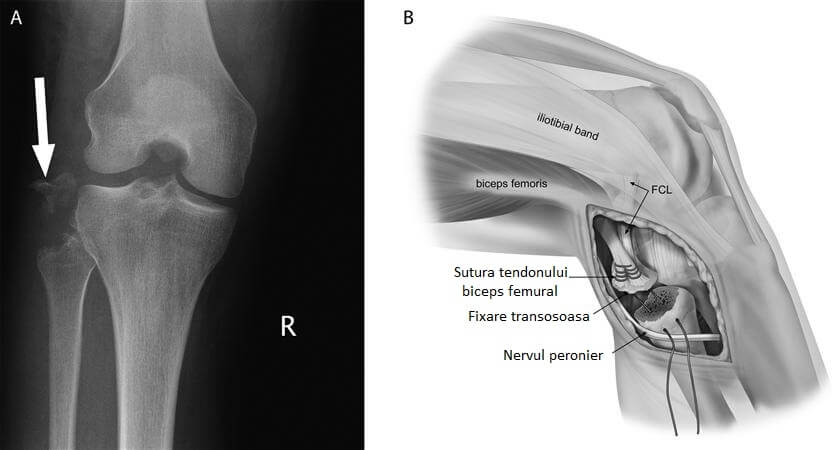

Tehnica chirurgicala efectuata de echipa noastra:

Se practica o incizie de cca 7 cm in zona laterala a genunchiului, se evidentiaza tractul iliotibial, muschiul biceps femural si nervul peronier comun, care se izoleaza. Se incizeaza tractul iliotibial si se evidentiaza epicondilul femural lateral. Se efectueaza 2 tuneluri osoase cu distanta dintre ele de 18mm si diametrul de 6mm.

Ulterior, se evidentiaza capul peroneului si se efectueaza un canal de 6mm oblic antero-posterior. Un alt canal postero-anterior se realizeaza prin tibie, folosind un ghid special, cu diametru de 9mm si lungimea egala cu diametrul tibiei.

Se recolteaza muschii semimembranosi de la ambele picioare, se fixeaza in canalele femurale cu 2 suruburi de 7/25mm, apoi tendonul fixat in canalul femural posterior este adus pe tractul iliotibial si fixat in capul peroneului cu 1 surub de 6mm in 20 de grade de flexie, iar la final, ambele tendoane ramase libere sunt fixate in tibie cu un surub de 10mm in 60 de grade de flexie.